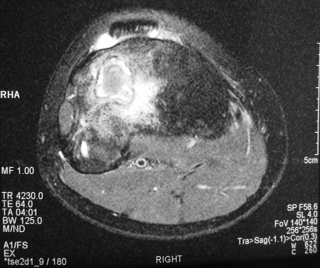

MRI (Fig. 4-7)

• Central low signal intensity with peripheral enhancement on T1-weighted images

• Heterogeneous high signal intensity with low signal in surrounding sclerotic bone on T2-weighted images

Fig. 4

Fig. 4-7: MR imaging of a benign fibrous histiocytoma of the proximal tibia demonstrates a heterogeneous high signal intensity and low signal intensity with surrounding sclerotic bone on T2-weighted images. T1-weighted images show low signal intensity. No soft tissue mass is visible.